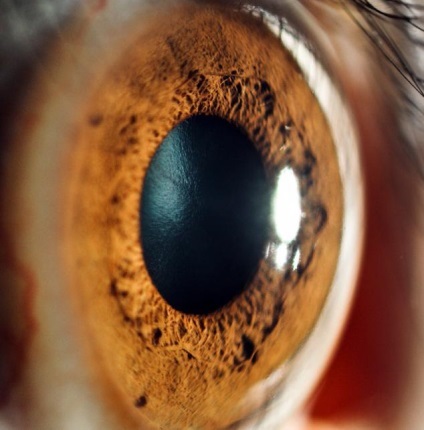

Sub cornee este iris, care oferă culoarea ochiului uman. În centrul pupilei este capabil de a schimba dimensiunea în funcție de iluminat. Intre cornee si iris este umoarea apoasă, care protejează microbii de cornee.

Acest corp ca o lentilă biconvexă, suprafețele față și spate din care au curburi diferite. Partea centrală a fiecăreia dintre ele - un pol care conectat axa. lungimea axei de aproximativ 3,5-4,5 mm. Ambele suprafețe sunt îmbinate de-a lungul conturului, care se numește ecuator. Adult are dimensiuni lentila ochiului optic 9-10 mm, acoperă capsula transparentă superioară (sac anterior), în interiorul căreia există un strat de epiteliu. Pe partea opusă se află capsula posterioară, aceasta nu are un astfel de strat.